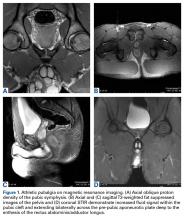

Patients with positive history and physical examination findings proceed through an MRI protocol designed to detect pathology of the pubic symphysis, hips, and inguinal canals (Figures 1A-1D).

Figure 1.